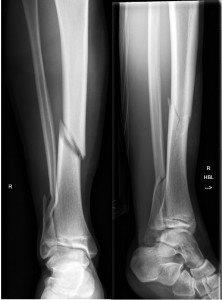

Undisplaced transverse fracture of tibia (arrow left)

Spiral fracture of tibia with minimal displacement